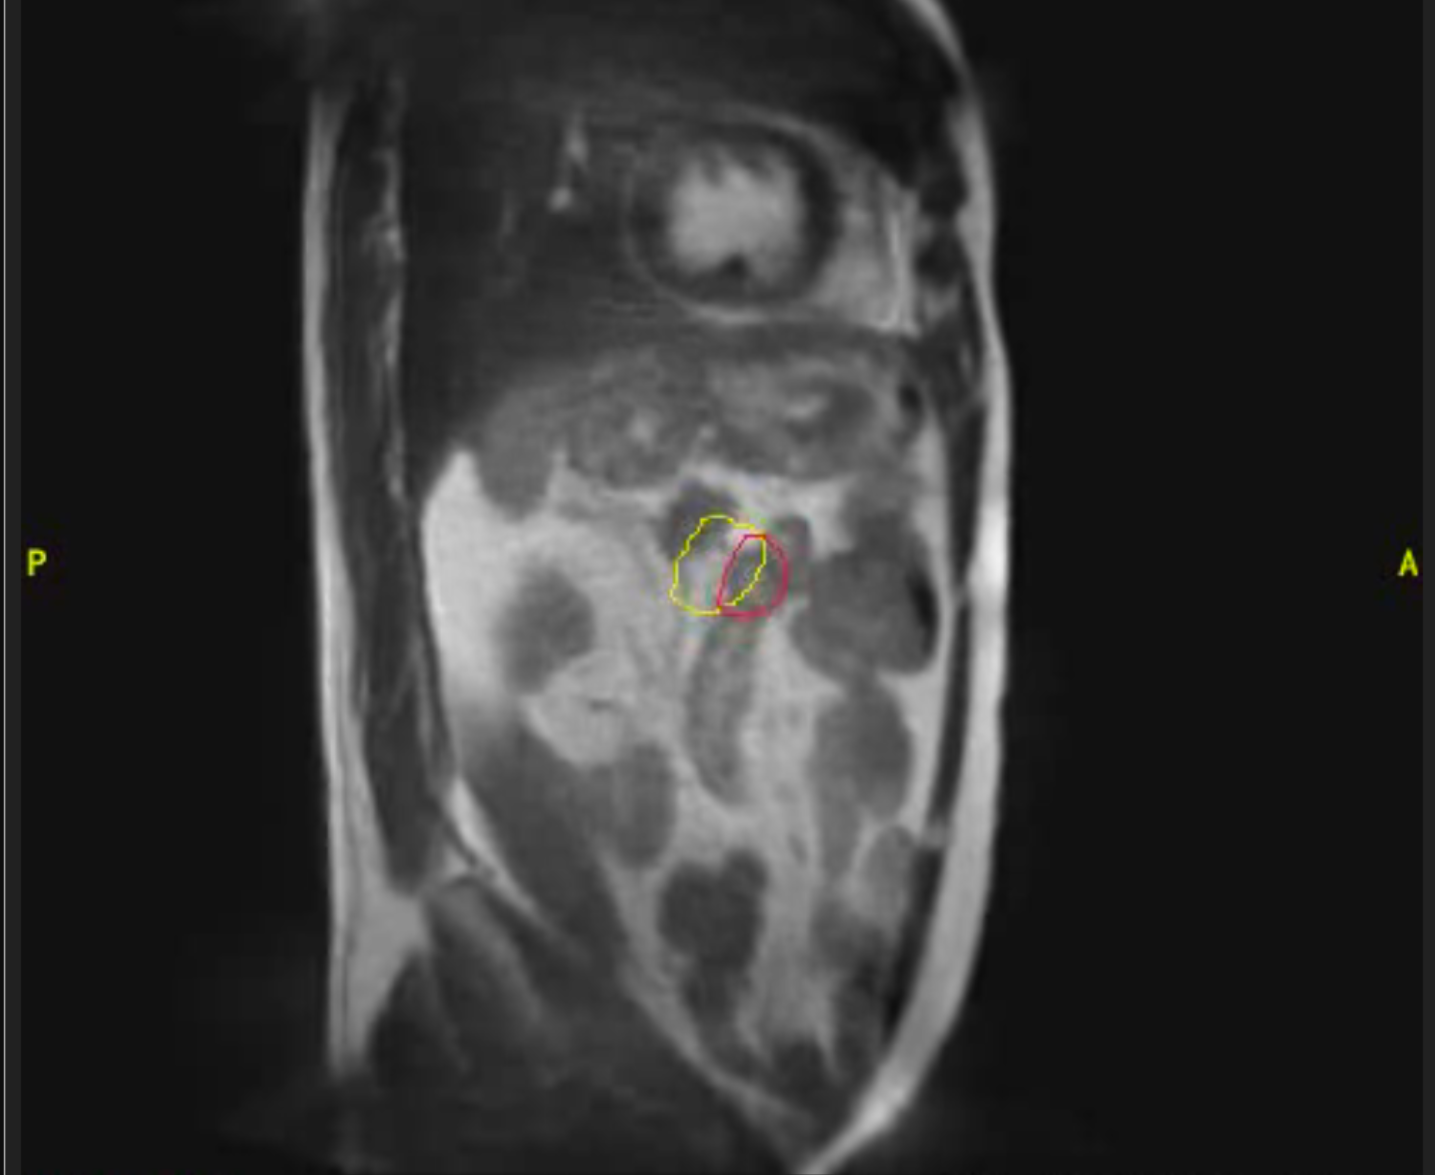

Cáncer de próstata

Varón de 85 años con diagnóstico de adenocarcinoma de próstata de bajo riesgo. Recibe tratamiento radioterápico con intención curativa en Acelerador Lineal con Resonancia (MRIdian): 5 fracciones en 5 días. Buena tolerancia, no efectos adversos destacables salvo ligero escozor al orinar autolimitado durante una semana.

Imagen 1